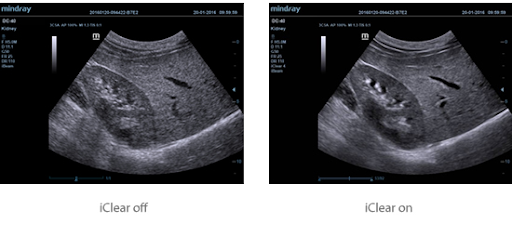

iClear

Улучшение качества изображения за счет автоматического определения характера ткани

-

Более четкие контуры без разрывов

-

Плавное и однородное отображение тканей

-

Снижение зернистости в областях без эхосигналов